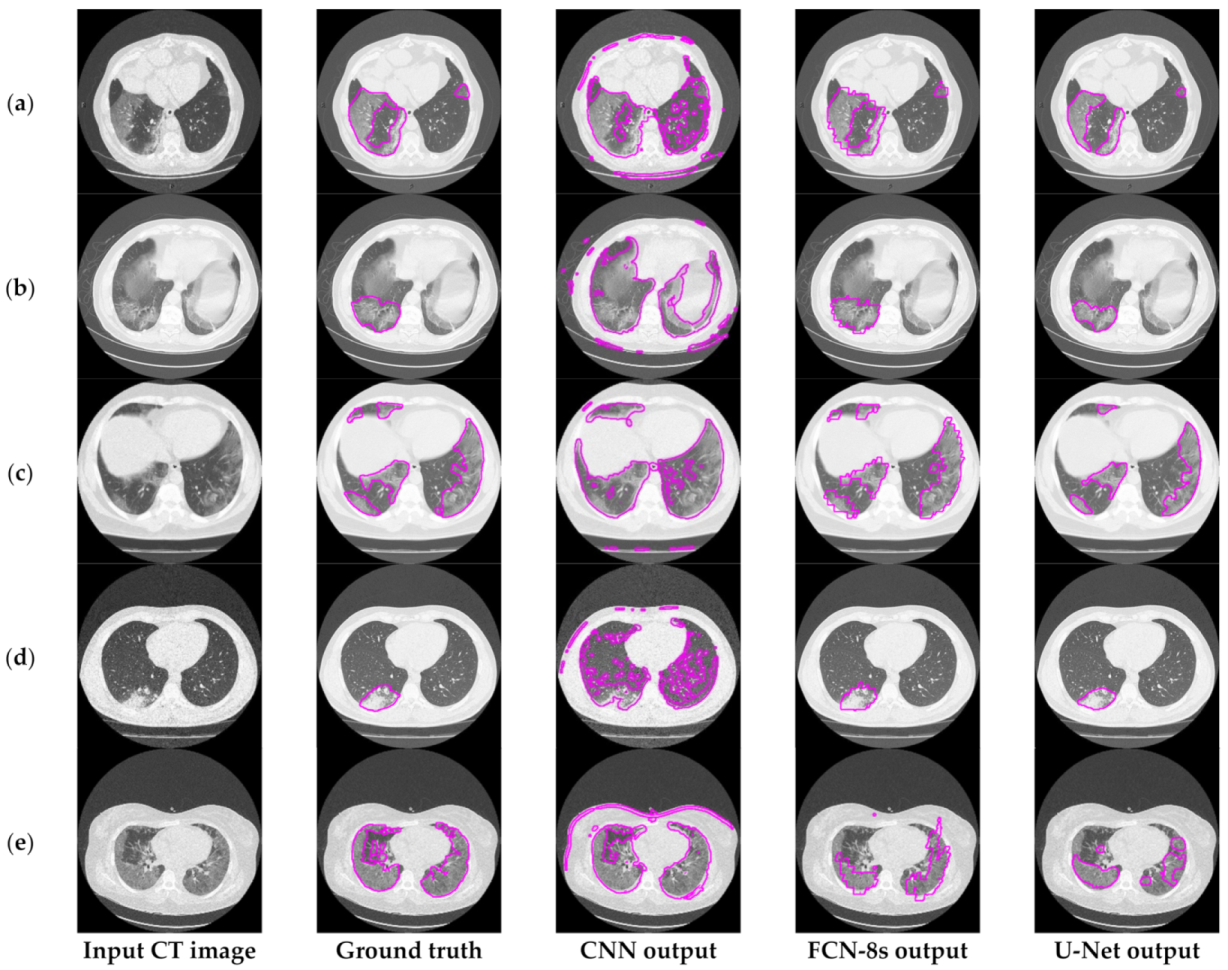

6.3.1. Comparisons with Other Deep Learning Models